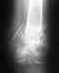

08.07.2010 г. в быту по неосторожности получил травму правого плечевого сустава, по поводу чего немедленно обратился в травмпункт, где после рентгенографии и осмотра врачом был госпитализирован в травматологическое отделение с диагнозом: оскольчатый перелом хирургической шейки правой плечевой кости. 09.07.2010 г. был прооперирован остеосинтезом металлоконструкцией Т-образной пластиной, которая не устранила повреждения.

Воспалительных послеоперационных осложнений не отмечалось. Гипсовую иммобилизацию удалили и провели рентгенконтроль 19.08.2010 г., который показал неудовлетворительную репозицию металлоостеосинтезом, сохранение перелома хирургической шейки плеча с захождением отломков костного дистального фрагмента кверху и наличием свободнолежащего костного фрагмента в полости сустава. Дистальные отделы шурупов в полости сустава. Подвывих головки плечевой кости книзу, суставная щель расширена до 3-х см. В настоящее время нахожусь на лечении в отделении реабилитации с диагнозом: закрытый оскольчатый перелом хирургической шейки правого плеча со смещением отломков. Операция МОС. Вторичное смещение отломков – сохраняется переломо-вывих в правом плечевом суставе с наличием металлоконструкции. Смешанная контрактура правого плечевого сустава, ФНС III ст. Осложнение основного диагноза: вторичное смещение отломков правой плечевой кости, миграция металлоконструкции. Стойкая смешенная контрактура правого плечевого сустава, ФНС III ст. Тугоподвижность правого локтевого сустава ФНС II ст. стойкий умеренный болевой синдром. Сам врач терапевт, на весь город 2 травматолога, уважаемые коллеги как можно оценить профессионализм оператора и прогноз, вычитал, что рекомендовано удаление металлоконструкции и однополюсное протезирование плечевого сустава в условиях специализированного отделения.

В любом случае, без свежих рентгенограмм начать обсуждение не получится.

Спасибо! Я врач терапевт, надеюсь на оптимальный исход и высылаю ссылку на архив рентгенограмм,контрольные находятся во 2 томе http://files.mail.ru/TZ2XHY

Действительно, тут лучше пластину убрать.

При ревизионной операции поглядеть, возможно, получится попытка реконструкции из того, что осталось. Эндопротезирование, пожалуй, наиболее практичный вариант.